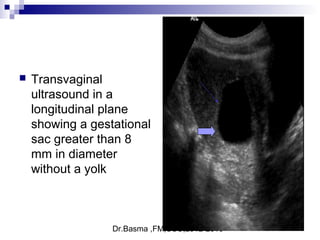

 Transvaginal

ultrasound in a

longitudinal plane

showing a gestational

sac greater than 8

mm in diameter

without a yolk

Signs suggestive of abnormal embryonic developmentSigns suggestive of abnormal embryonic development

 include a gestational sac greater than 10 mm10 mm in diameter without a visible

yolk sac